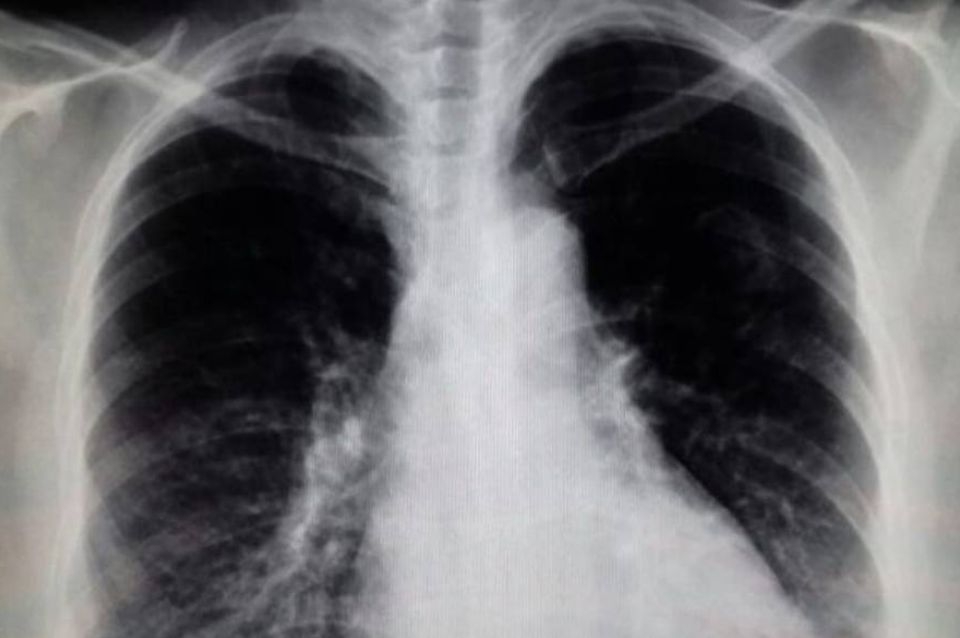

Día Mundial de la EPOC: cerca del 80% no sabe que la padece

La Enfermedad Pulmonar Obstructiva Crónica (EPOC) es una condición respiratoria prevenible y tratable caracterizada por una persistente limitación al flujo aéreo (obstrucción), la cual puede presentar algún grado de reversibilidad, pero en ningún caso normalizarse.

Esta enfermedad, caracterizada por la obstrucción de las vías respiratorias que limita la circulación del aire, está relacionada con el tabaquismo, antecedentes de infecciones respiratorias y factores medioambientales, como la contaminación, los alérgenos y la altitud.

Es necesario destacar la importancia de la espirometría, ya que permite a los médicos detectar la afección en estadios tempranos y brindar un tratamiento que minimice el impacto en la salud. Este control es especialmente importante para las personas con antecedentes de tabaquismo prolongado, que son quienes tienen mayores probabilidades de desarrollar complicaciones respiratorias severas. De hecho, el 90% de los casos existentes son producto de la exposición al humo del cigarrillo.